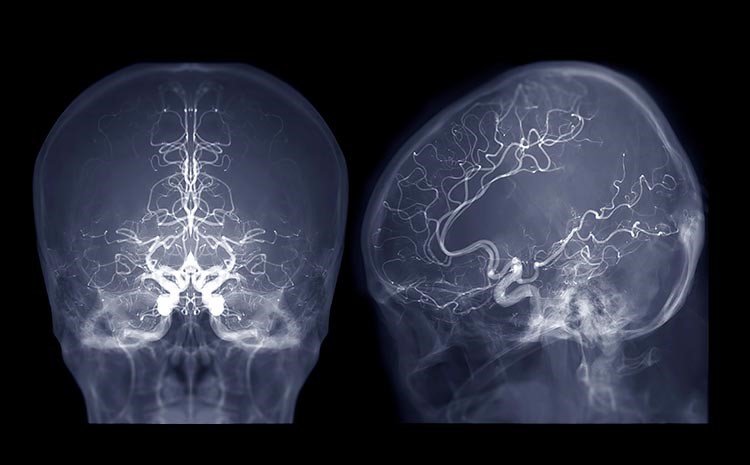

A neurocirurgia vascular é a subespecialidade da neurocirurgia dedicada ao tratamento das doenças que afetam os vasos sanguíneos do cérebro e, em alguns casos, da medula espinhal. Esses vasos podem apresentar dilatações, obstruções, rupturas ou conexões anormais.

A trombectomia mecânica é um procedimento endovascular indicado em casos selecionados de obstrução de grandes artérias cerebrais. Por meio de um cateter introduzido pela artéria da perna ou do braço, o coágulo é removido.

No tratamento endovascular, um cateter é introduzido pela artéria femoral ou radial até o cérebro. Dentro do aneurisma são colocadas espirais ou dispositivos específicos que o isolam da circulação.